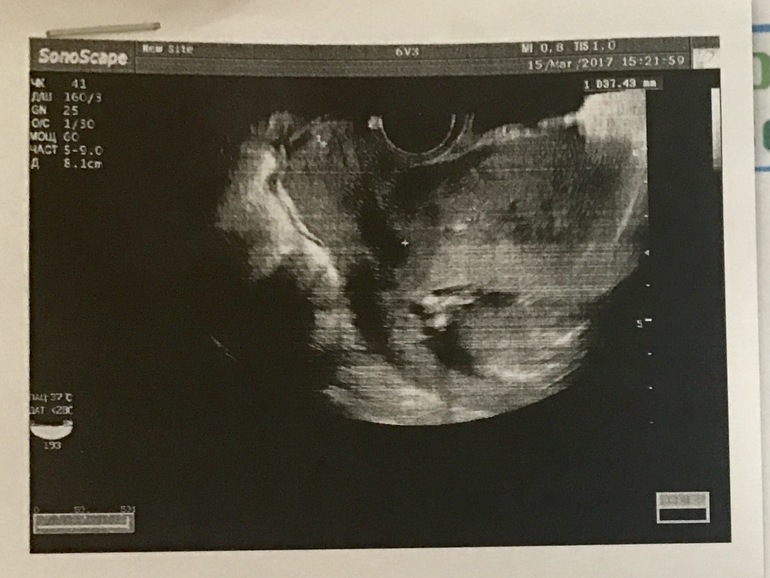

что вообще на фото?

Сегодня срочно нужно было сходить на УЗИ не к своему доктору (вчера упала)

Смотрели вагинально. Попросила глянуть пол малыша. Слышала про доктора, что она глазастая узистка и знакомым пол ребёнка говорила чётко в 12 недель. Я так ждала , она вертела, вертела, а потом сказала, что видно плоховато (не знаю почему именно) но больше похоже на девочку, чем на мальчика.

Дала распечатку фото, но я понятия не имею что это вообще как на нем.

И глазастых прошу рассмотреть записи в левом углу. Там в конце есть параметр Д -8,1см, это длина ребёнка? Или это данные датчика этого))) Полностью или КТР? Она так быстро все делала и улетела. Я мало что поняла. Главное конечно, что кроха здоров и у меня все хорошо. Сердечко 142 удара)